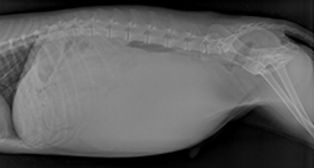

Image courtesy of https://www.acvs.org/small-animal/splenic-masses/

Splenic masses may sometimes be detected during a physical examination of your pet's abdomen, or through an X-ray to locate the tumour. Additional diagnostics can include blood tests for anemia and ultrasounds to pinpoint the affected organ.